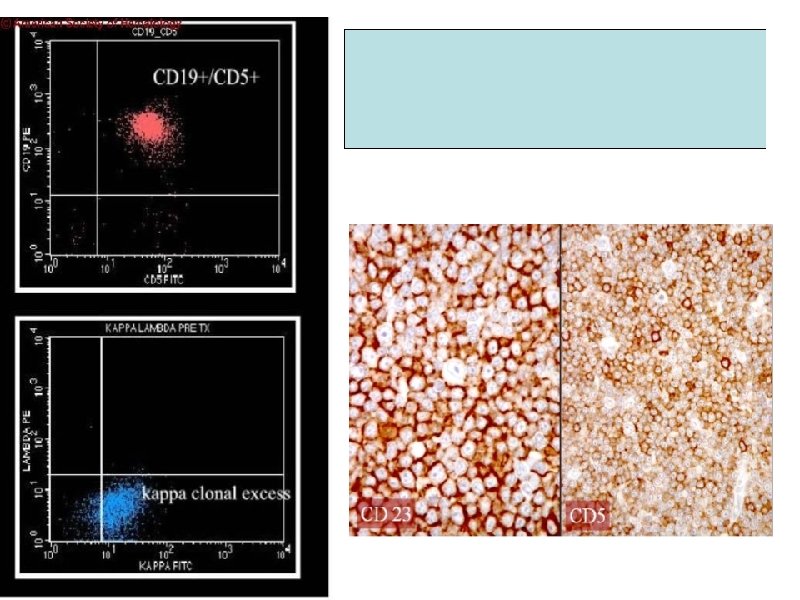

Гистологическая картина костного мозга при ХЛЛ